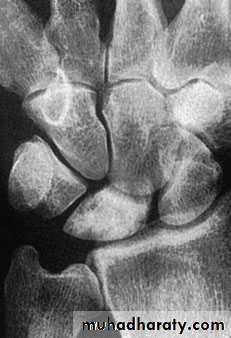

KIENBOCK’S DISEASE

a form of ischaemic necrosis, probably due to chronic stress or injury

Pathology:the pathological changes proceed in four stages

Clinical features:

Imaging:

Radioscintigraphy may reveal

increased activity

X-rays

MRI